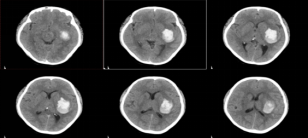

36岁的严某晚间突发头痛,随后肢体无力、意识障碍,被同事发现后,马上送到附近医院就诊。严某有高血压病史,当时她已意识朦胧,不能言语,右侧肢体瘫痪,肌力1级,血压高达210/118mmHg,头颅CT提示左侧基底节区急性脑出血约40ml,情况危急。

患者术前头颅CT

术后患者转入ICU继续治疗。经过常规镇静、镇痛等治疗,患者在术后第1天已恢复意识,能与外界交流。术后第3天就转回普通病房,此时她已能简单言语,右侧手脚可轻微抬起。经过血肿引流3天,复查头颅CT显示,血肿大部分被引出,达到理想效果,可拔除引流管。

患者术后一个月门诊复查头颅CT